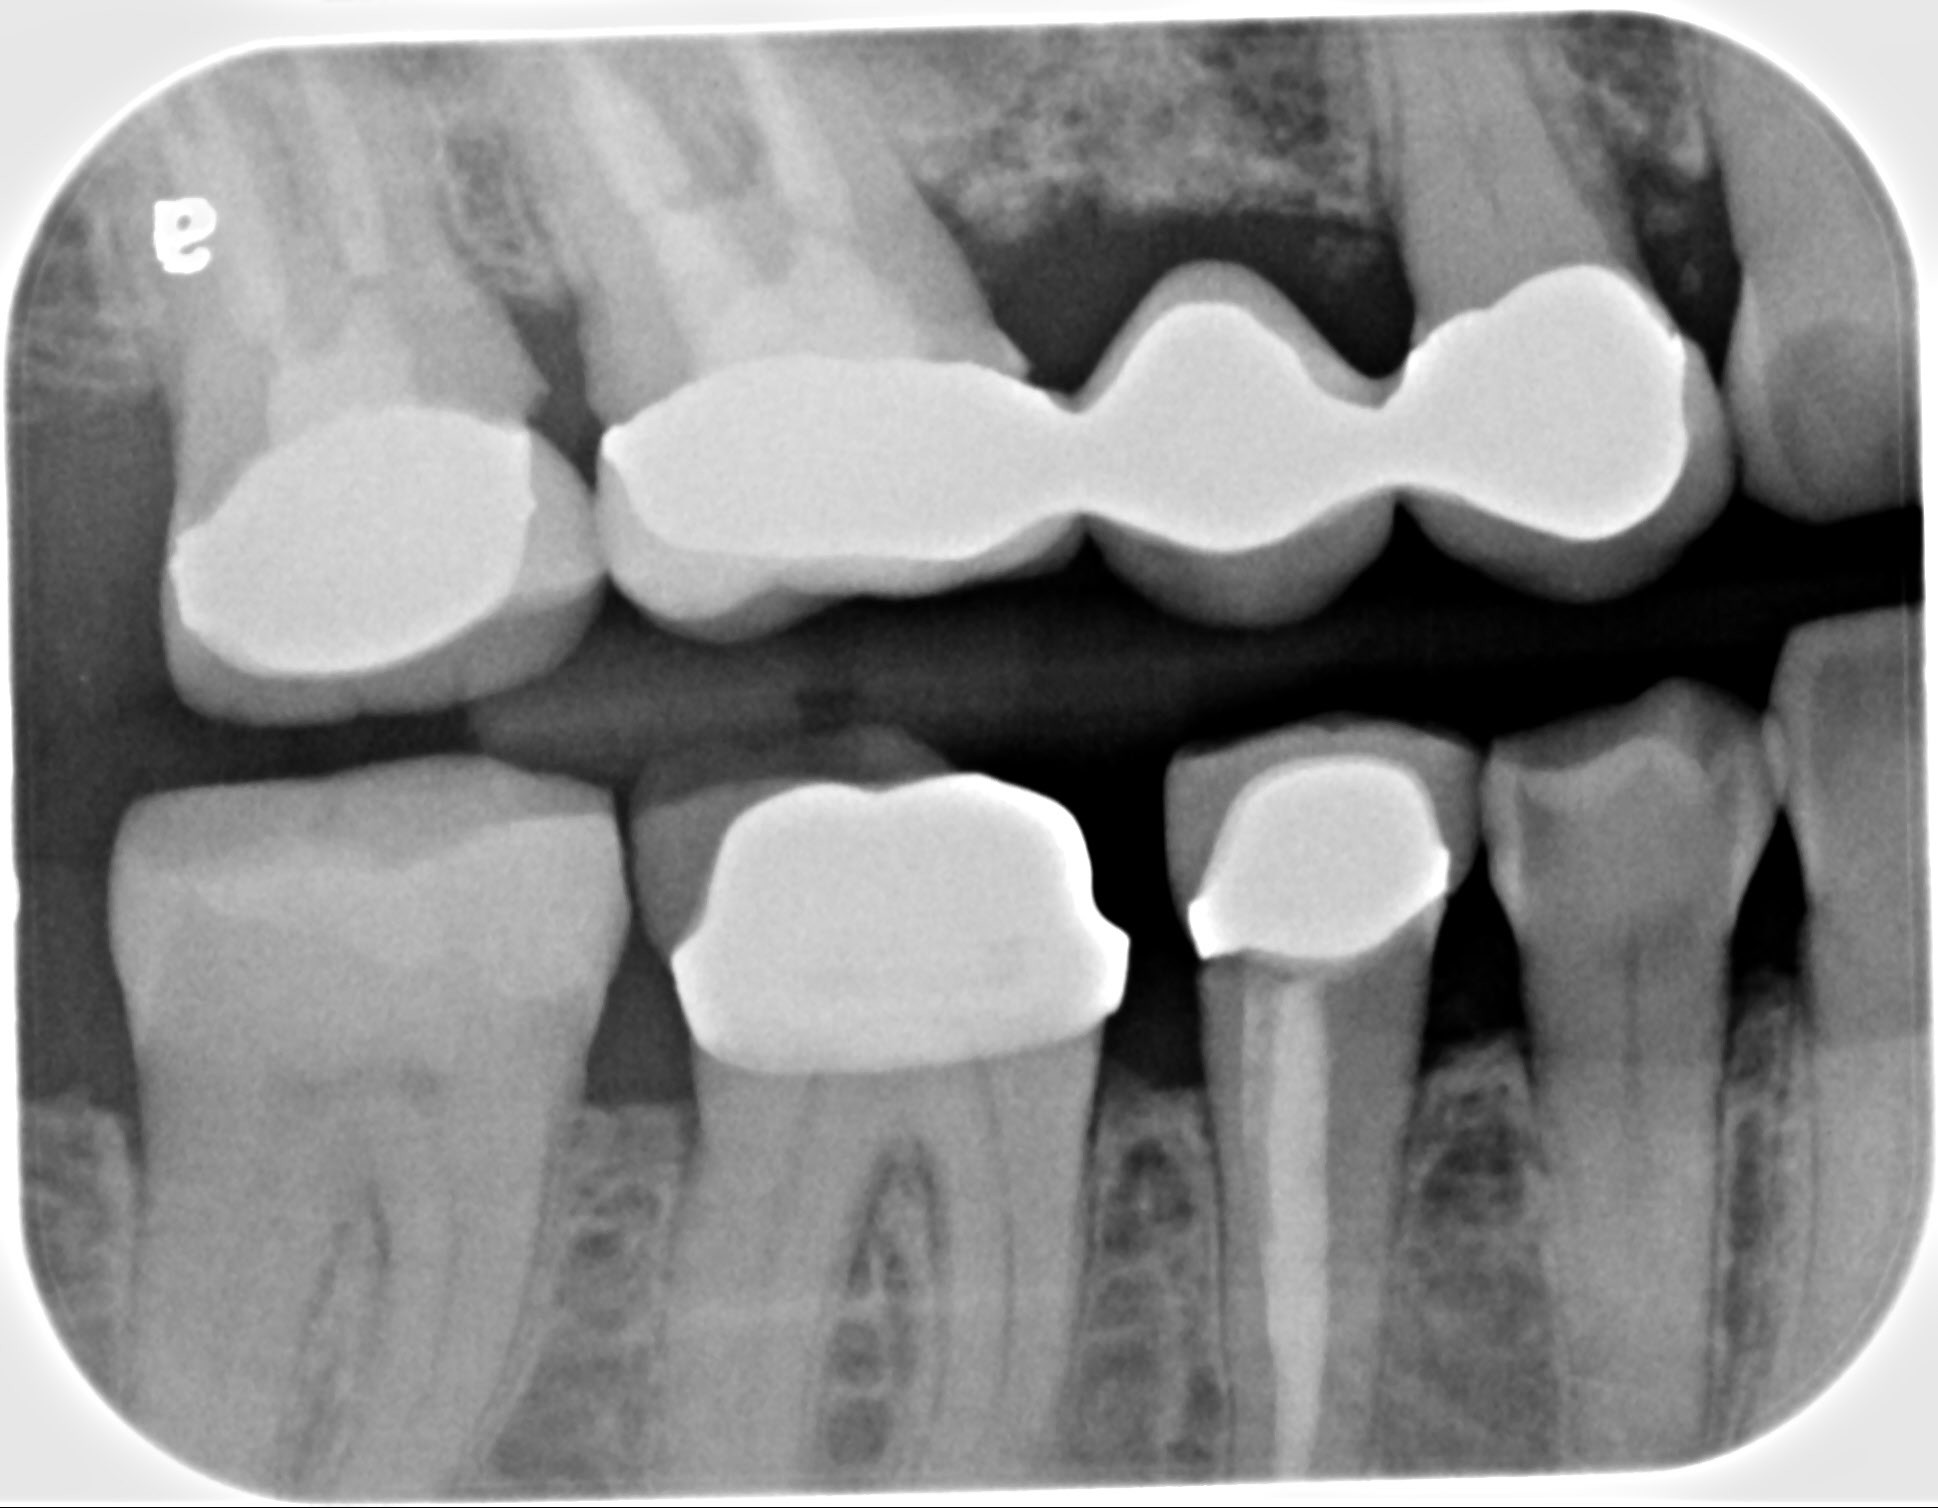

21. What option can be selected for the restoration on upper jaw?

27. What option can be selected for the restoration on the upper jaw?

32. What option can be selected for the restoration on the upper jaw?